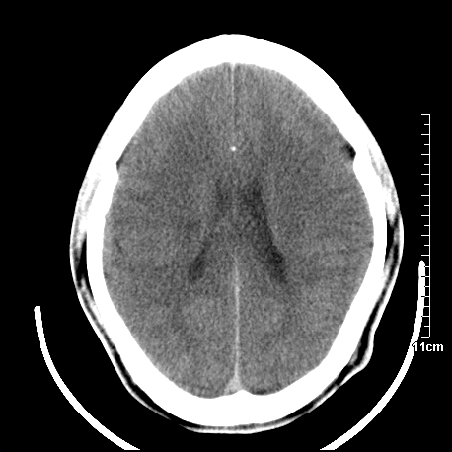

头晕.头痛间断意识恍惚1周 m/21y

4天上述症状加重伴左侧肢体发软,复查ct,

右侧放射冠可见点状低密度,可疑腔隙性梗塞

我当时诊断的是1.右侧底节区脑血栓形成

2.考虑少量蛛网膜下腔出血

3.右侧颞叶低密度区考虑脑血管畸形

因病人拒绝进一步检查,反复做工作后,病人做了腰穿,脑脊液化验显示有红细胞,呈现轻度红色

右侧基底节区低密度灶,建议磁共振检查。

右侧放射冠区混杂密度灶,边缘不清,病人较年轻,结合有发热病史,支持感染性病变,建议密切结合临床可抗感染治疗后复查。

右侧颞叶病变定性困难,既然发病急,又有发热,脑脓肿不能除外。

右侧颞叶混杂密度灶,强烈建议:增强ct检查